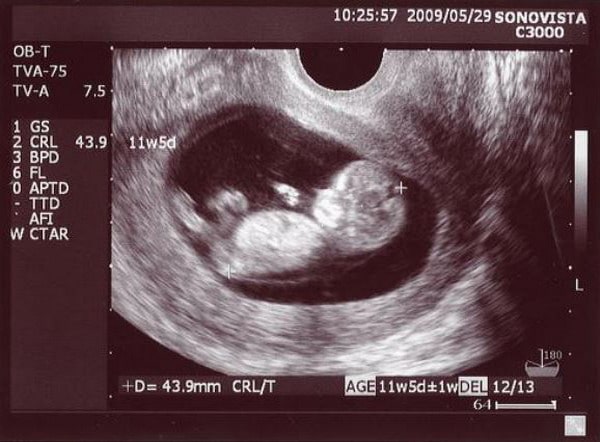

11 haftalık gebelik